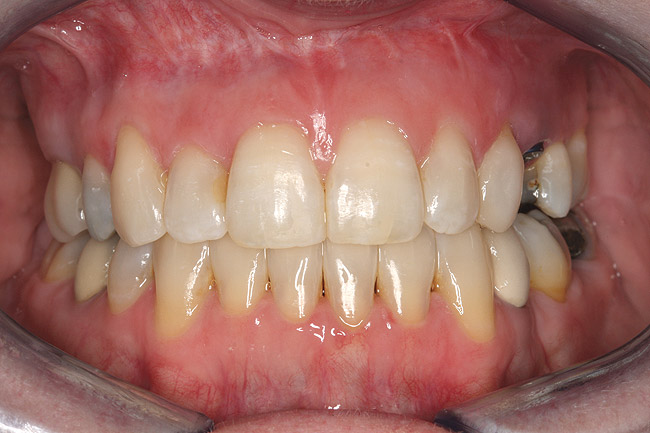

Fig 16 (and Fig 17). Anterior deep bite with extruded and retruded anterior dentition secondary to unstable relationship.

Figure 16

Fig 17 (and Fig 16). Anterior deep bite with extruded and retruded anterior dentition secondary to unstable relationship.